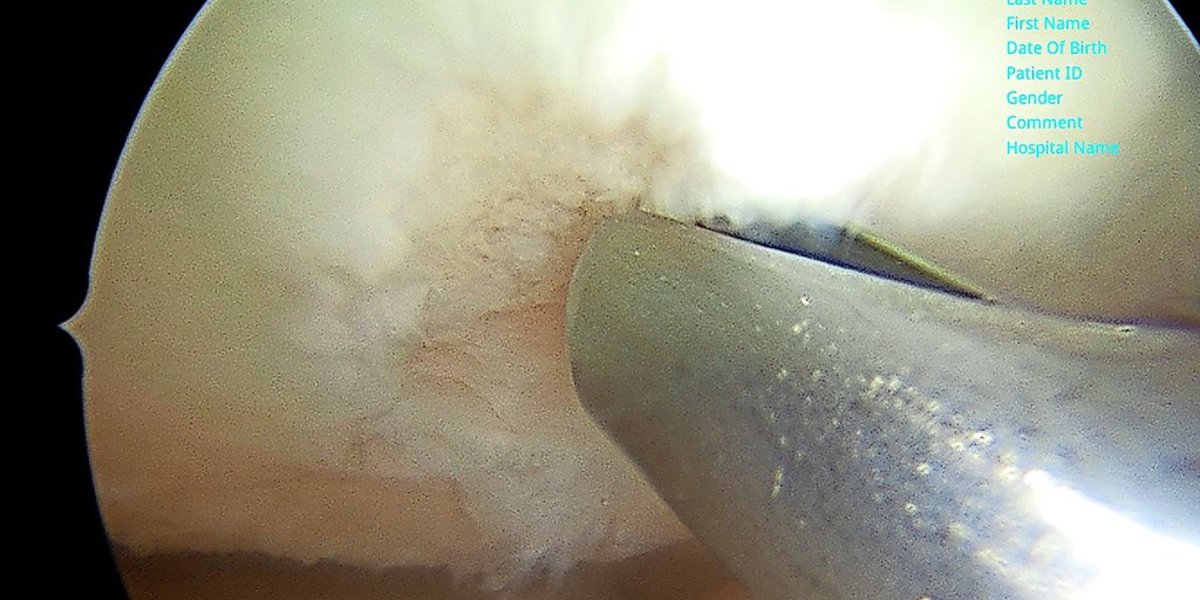

Um bei schwerwiegenden Knorpelschäden seltener künstliche Kniegelenke einzusetzen, wenn konservative Methoden nicht zum Erfolg führen oder Patienten sie nicht bezahlen können, setzt Warzecha – vor allem bei Patientinnen und Patienten unter 65 Jahren –, inzwischen auf einen aus der ACP-Therapie weiterentwickelten Eingriff, der in den USA seit gut fünf Jahren angewandt wird, in Deutschland aber noch nicht weit verbreitet ist. In Hildesheim ist Warzecha bisher der einzige Arzt, der die AutoCart genannte Methode praktiziert. Es geht auch um einen operativen Eingriff, der findet aber minimalinvasiv statt und soll möglichst zum Erhalt des Gelenks führen. „Die Knorpel-Chirurgie ist wirklich ein tolles Verfahren. Das sollten wir den Patienten nicht vorenthalten“, sagt Warzecha. Gerade bei Jüngeren – die Altersgruppe 45 bis 60 Jahre – sollte man Prothesen möglichst vermeiden. „Ein künstliches Gelenk hält maximal 20 Jahre und bei jeder OP wird der Eingriff größer. Vor 65 sollte man möglichst auf Implantate verzichten.“

Vereinfacht gesagt passiert bei der AutoCart-Methode dies: Der Chirurg schabt aus dem großflächig beschädigten Knieknorpel Gewebe heraus, filtert Knorpelzellen heraus, ehe die gereinigte Masse mit aufbereiteten Blutbestandteilen des Patienten zu einer Paste vermischt wird. Diese trägt der Arzt dann auf den Knorpel auf und verschließt somit die beschädigte Stelle. Der Eingriff ist deutlich weniger aufwändig, dauert nur rund 45 Minuten, zudem trägt der Patient hinterher keinen Fremdkörper in sich. „Es ist alles körpereigenes Material, das benutzt wird“, sagt Warzecha. „Ein optimales Verfahren.“ Der Hildesheimer wendet die Methode seit gut einem Jahr an, hat bisher zwölf Personen mit der AutoCart-Methode behandelt; die Resonanz sei bisher positiv. Wichtig sei, dass Patienten das Knie direkt nach der OP schonen und anschließend durch Physiotherapie beweglich machen und gezielt stärken. „Es gibt ein strenges Nachbehandlungsregime“, stellt der Chirurg klar. Die beste OP bringe wenig, wenn Patienten sich hinterher nicht an die Vorgaben halten. Warzecha ist sich sicher: „Wer so etwas auf sich nimmt, der tut alles dafür, dass es gelingt.“